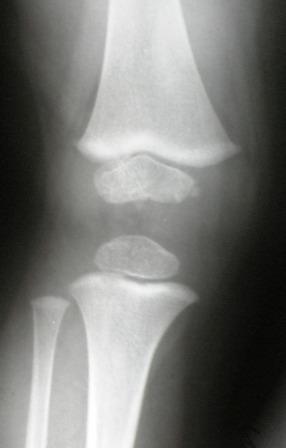

Уважаемые коллеги! Помогите уточнить диагноз. На ортопедический прием мама привела упитанного 3 летнего мальчика. Родился и рос нормальным ребенком. Последнее время стал жаловаться на ножки. Мама заметила Х-образную деформацию нижних конечностей. При осмотре отмечена легкая вальгусная деформация коленных суставов, плоскостопие. Предполагаю, что это МЭД - множественная эпифизарная дисплазия. Р-грамма прилагается. Какие варианты лечения?. С уважением Виктор

При более близком рассмотрении Рг создается впечатление неоднородности структуры зоны роста в латералных отделах дист. бедра при нормальной

структуре медиальной пластинки. Эпифизы, на мой взгляд, выглядят вполне симметричными и не измененными.

Уважаемый Евгений! Спасибо за обстоятельный совет. Обязательно сделаю КТ или МРТ. Неоднородность структуры зоны роста я, к сожалению, не заметил. По-моему, возникают ассоциации с механизмом развития избыточной антеверсии шейки бедра. Но, все-таки у меня остается впечатление «сжатости» метафизов, особенно бедра.

Для иллюстрации привожу пример из «Нормальной рентгеноанатомии костно-суставной системы детей». В. И. Садофьева. ЛЕНИНГРАД «МЕДИЦИНА» 1990

^^^^^^^^сурово ;) В любом случае одних снимков коленных суставов для такого вывода недостаточно. По снимкам- норма